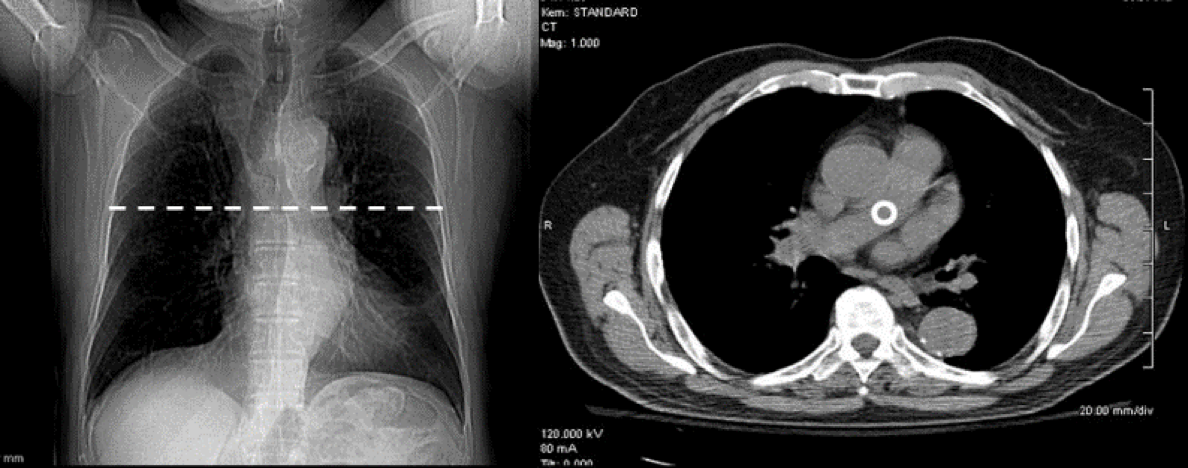

Unlike traditional radiography, which produces projectional images of structures superimposed on each other, CT visualizes slices of the patient only a few millimeters thick, eliminating the problem of superimposition.

CT is usually performed in the axial plane, but it is possible to reconstruct excellent images in other planes, e.g. coronal , sagittal or oblique, and even three-dimensional (3D) images

A CT scan produces a greyscale image, with high-density material appearing bright (e.g., bone) and low-density material appearing dark (e.g., fat).